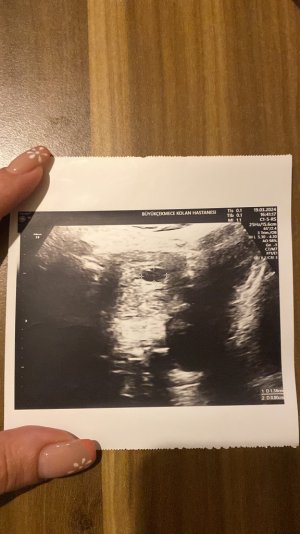

19 Mart’ta gebelik kesem 1.38 cm idi pazartesi gel ve kalp atışına bakalım dedi doktorum ve bugün gittik keseye baktı ve kalp atışı henüz oluşmamış dedi. Kese ölçüm 1.42 cm bugün.

19 Mart’ta gebelik kesem 1.38 cm idi pazartesi gel ve kalp atışına bakalım dedi doktorum ve bugün gittik keseye baktı ve kalp atışı henüz oluşmamış dedi. Kese ölçüm 1.42 cm bugün.